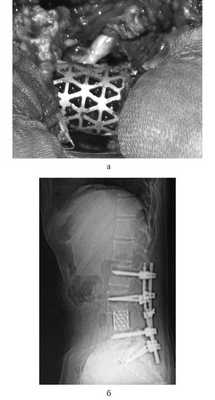

Для замещения удаленных позвонков у 8 (28%) больных применен сетчатый титановый протез «MASH» (рис. 1), который использовался нами с 2006 по 2010 г. Телескопическая система эндопротезирования, которая использовалась с 2010 по 2016 г., применена у 21 (72%) пациента (рис. 2). Спондилодез при помощи пластин выполнен у 19 (65,5%) больных, комбинированная стабилизация (титановые винты и пластины) — у 10 (34,5%) пациентов.

![]()

Рис. 1. Вертебрэктомия позвонка LIV с замещением дефекта сетчатым эндопротезом тела позвонка системой «MASH» и транспедикулярной фиксацией. а — интраоперационная фотография; б — послеоперационная рентгенограмма поясничного отдела позвоночника.